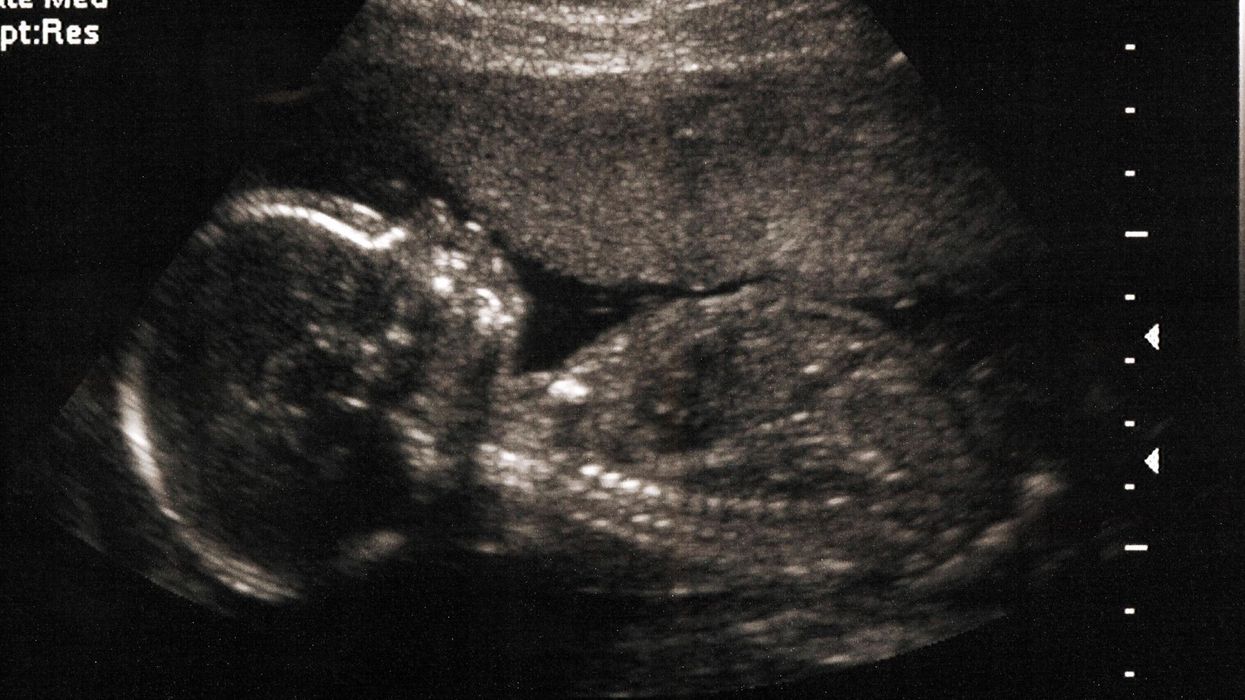

Picture:

iStock

The posted meme was taken from a Facebook page called “Life Begins at Conception” and features a picture of a baby, with the captions “If you’re pronounced dead when your heart stops beating… why aren’t you pronounced alive when your heart starts beating?” accompanying it.

Please do actual research before trying to use emotional manipulative photos of babies that are born and NOT foetuses before parading it out and believe it as fact.